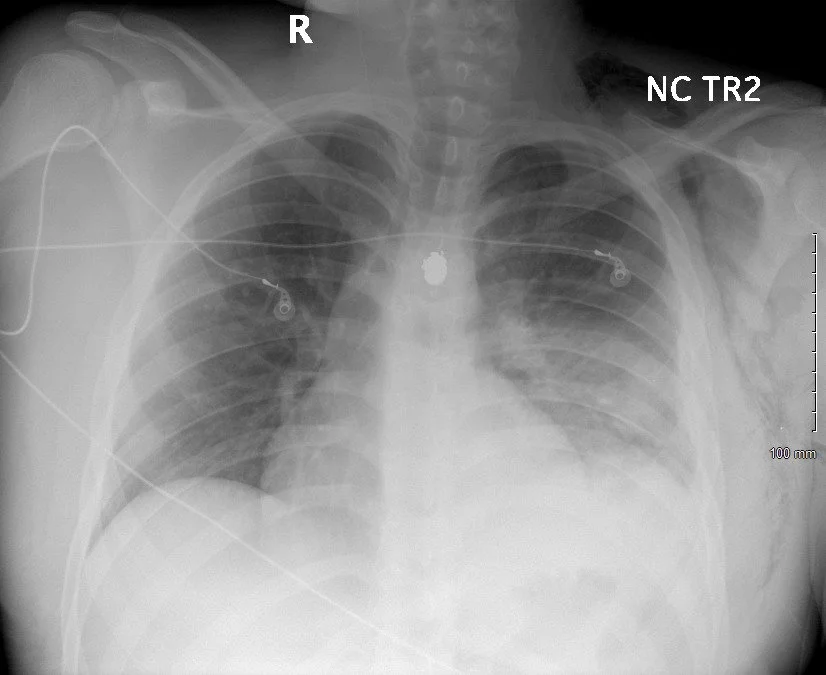

A young male is stabbed with a knife in the right upper back, he’s found on the street. NYPD is there prior to EMS, picks him up, throws him into the back of their car and arrives screeching to a halt in your ambulance bay. No prehospital notification, a team of ED staff runs out and gets him on a stretcher and into the resuscitation bay where there’s a lot happening in unison; IV access, exposure, physical exam ect. He’s awake and alert, stab wounds to right upper back.

eFAST performed, no lung sliding on the right (clip 1) and good lung sliding on the left (clip 2). The patient has a right sided pneumothorax. The evaluation of the lungs (pneumothorax/hemothorax) has been a staple in trauma resuscitation since 2024, when the Focused Assessment of Sonography in Trauma (FAST) evolved to include an evaluation for pneumothorax / hemothorax, the eFAST; the extended Focused Assessment of Sonography in Trauma (eFAST).

Right sided thoracostomy was performed and the patient did well.